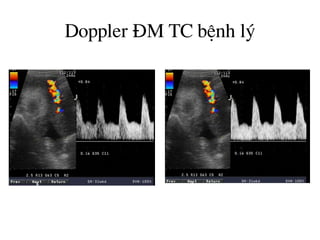

Doppler §M rèn bÖnh lý

Doppler §M TC bÖnh lý